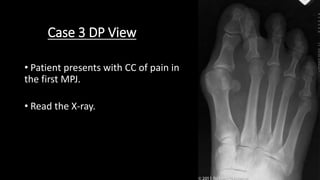

Case 3 DP View

• Patient presents with CC of pain in

the first MPJ.

• Read the X-ray.

Case 3

This is a dorsoplantar view of the right foot. The met

adductus angle looks within normal limits. The hallux

abductus (25 degrees) and intermetatarsal (17 degrees)

angles are increased. The hallux interphalangeal angle is

normal (0 degrees). The proximal articular set angle (PASA, 6

degrees) is high normal. The tibial sesamoid position is 7, and

the first metatarsal head medial eminence is prominent. The

proximal and distal articular set axes cross within the joint.

Other findings: The second toe angulates medially relative to

the second metatarsal and is superimposed upon the hallux

distally. The fourth toe is in adductovarus position.

Diagnoses: Hallux abductovalgus with bunion deformity and

overlapping second toe. Subluxation, first

metatarsophalangeal joint. Toe deformities.